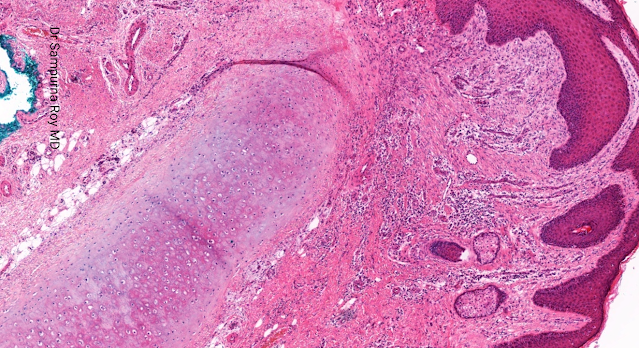

Dermatopathology Case 195 Get link Facebook X Pinterest Email Other Apps April 11, 2022 A 56 year old man presented with a painful ulcerated lesion on the right upper helix of 3 months' duration. Answer Get link Facebook X Pinterest Email Other Apps Comments